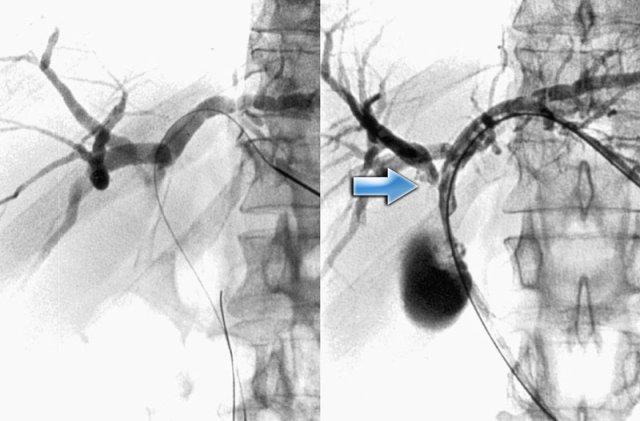

The cholangiogram is important in the work up of these patients, because obstruction has to be excluded.

This can be done with MRCP or ERCP, as is shown on the left.

There was no sign of obstruction.

The mild dilatation of the choledochal duct was the result of cholangitis.